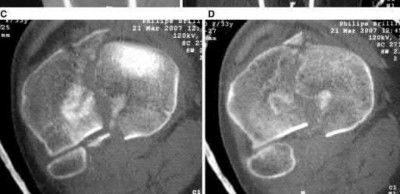

A 72-year-old woman falls down stairs and sustains the injury shown in Figure A. Additional radiographs are performed in Figure B to help assess the fracture pattern. These additional radiographs represent which of the following?

Additional traction radiographs are performed in distal humerus fractures to better understand the fracture configuration.

Traction radiographs help align the fracture fragments for better visualization. This is useful in comminuted fractures where distal fragments are telescoped or flexed on the proximal fragments, making CT scan visualization difficult.

Proper visualization can help determine (1) the approach to the distal humerus, (2) whether to perform ORIF or total elbow arthroplasty (in select patients), (3) whether to add a 3rd plate (lateral column), (4) whether to add tricortical bone graft to augment distal fixation and restore trochlear width.

Figures A and B show a distal humerus fracture without traction (A) and with traction (B) applied. Illustration A shows the same fracture after bicolumnar plating. Illustration B shows the different surgical approaches to the distal humerus (A, Campbell triceps splitting; B, O'Driscoll triceps reflecting anconeus pedicle [TRAP]; C, Bryan-Morrey triceps reflecting; D, olecranon osteotomy)